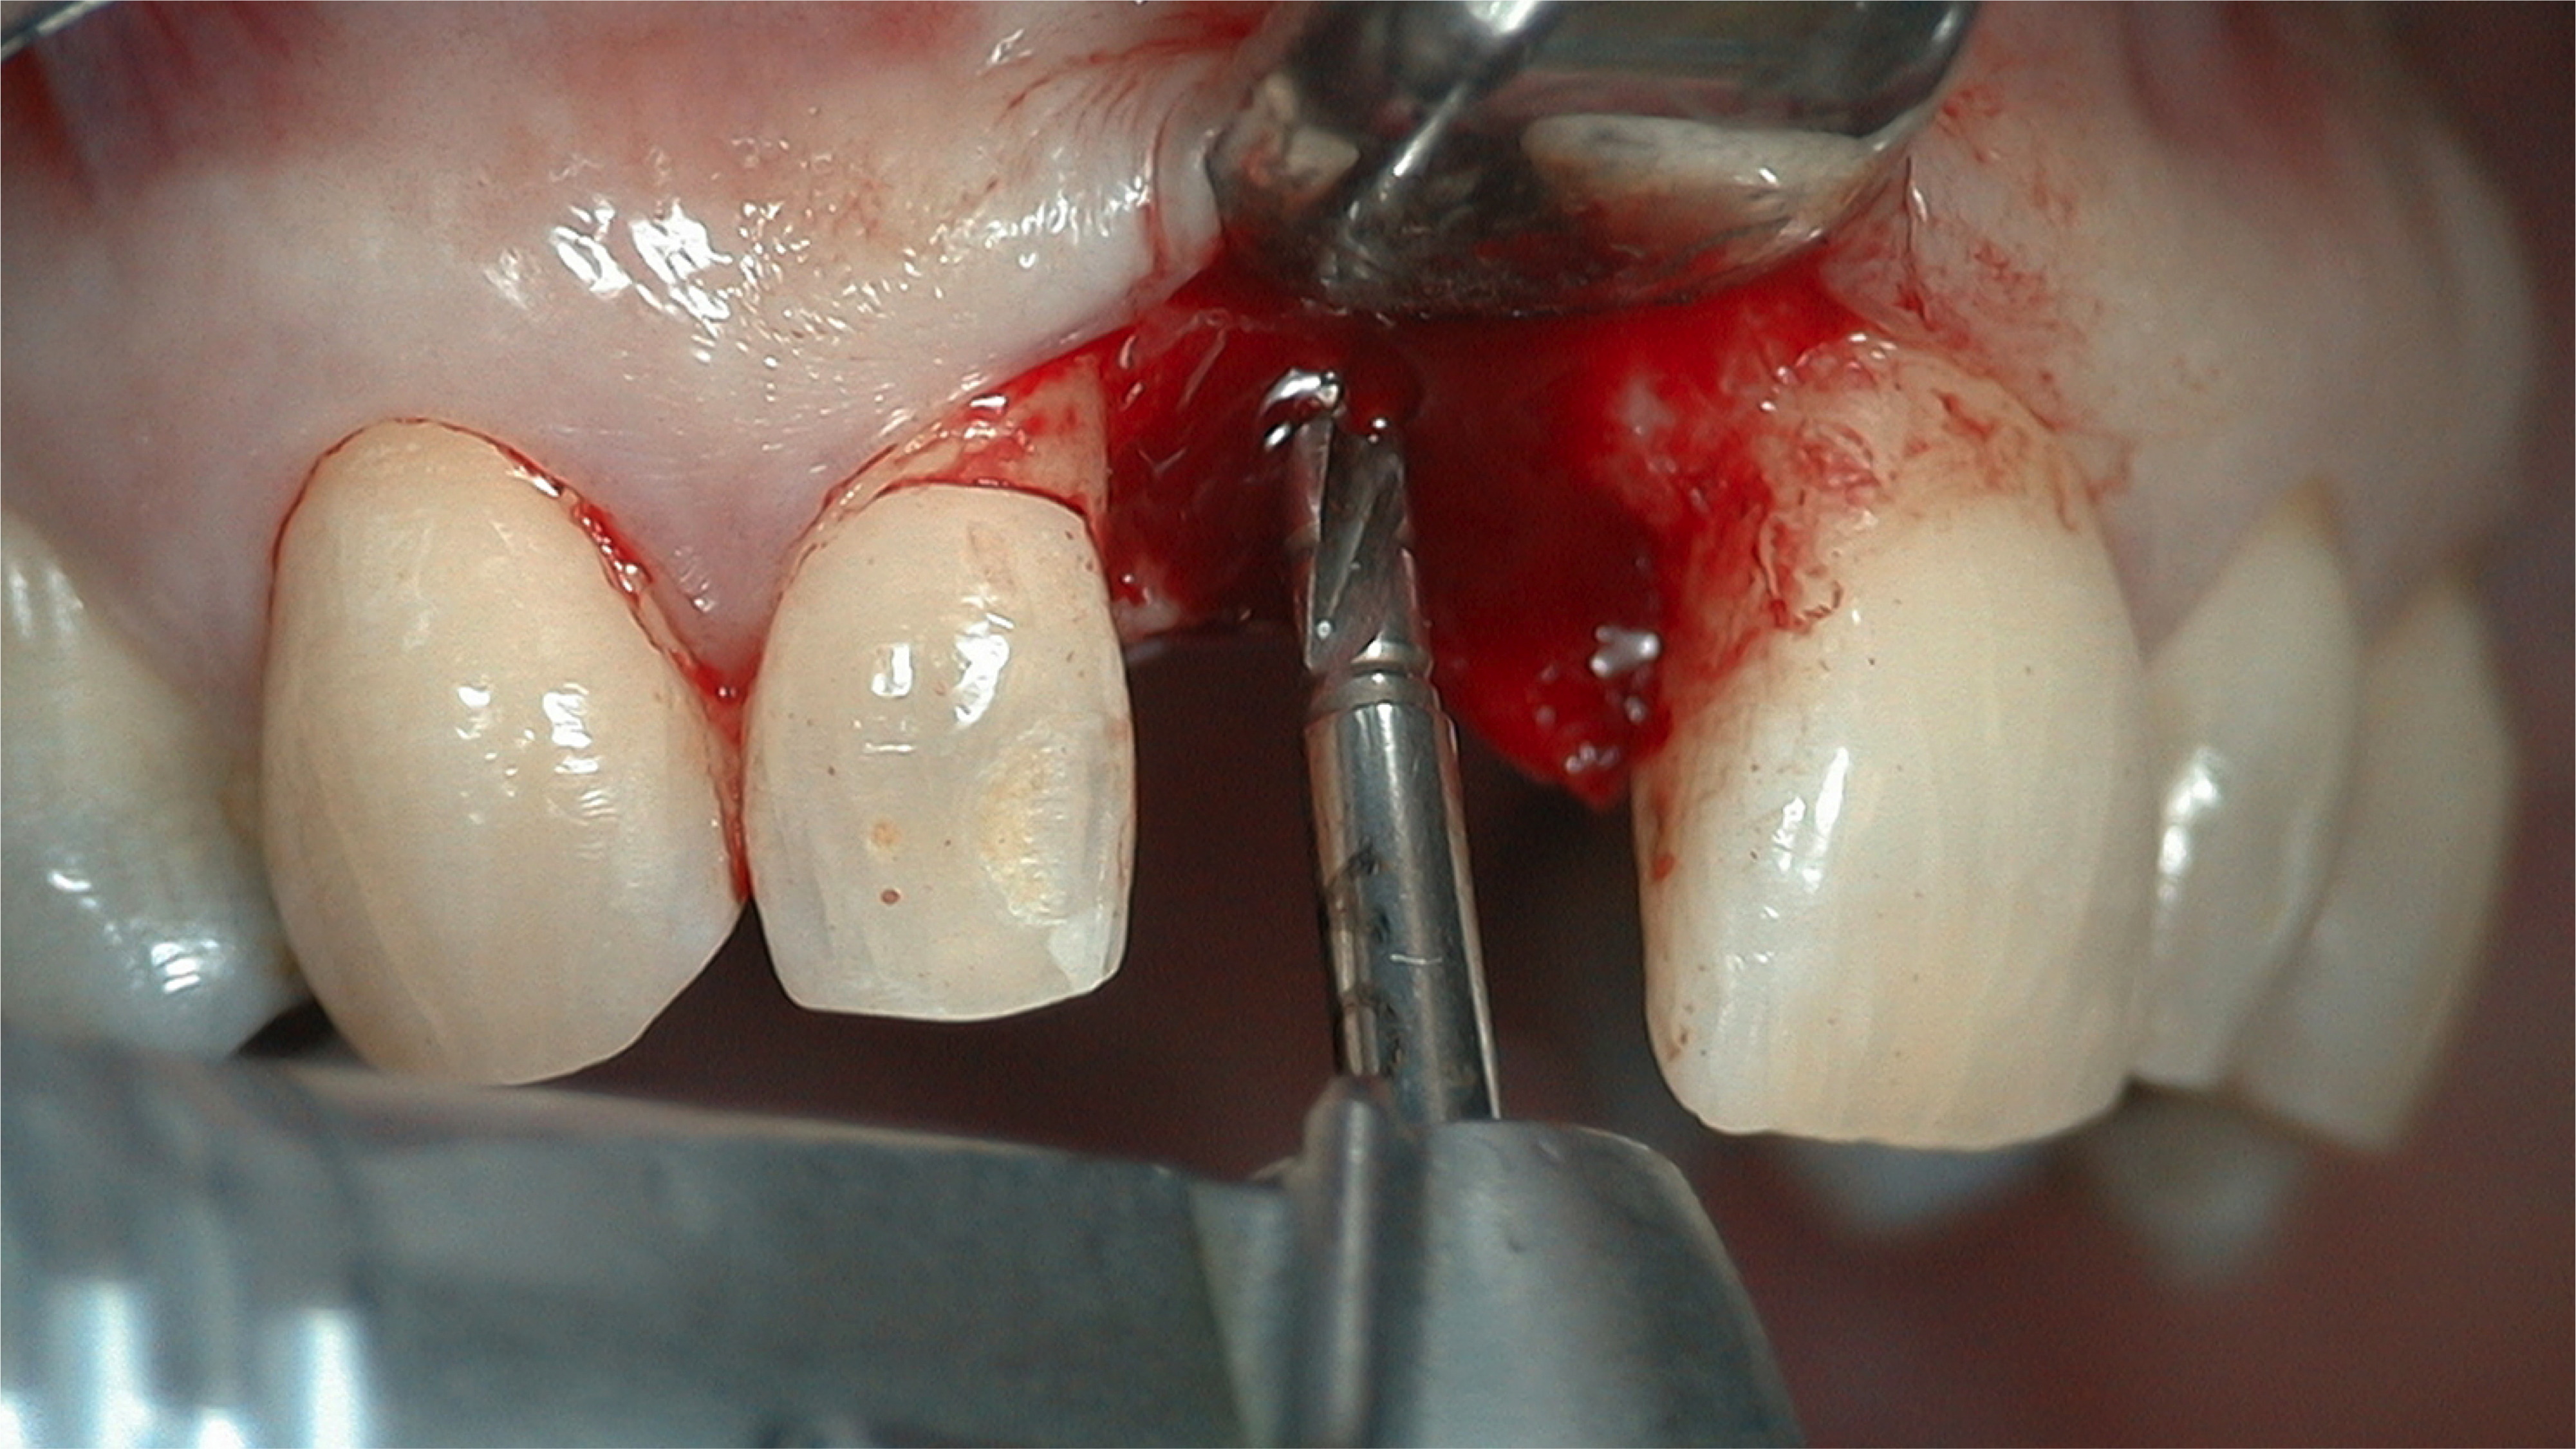

Fig 5. 1.5 mm of bone should surround the implant on either side.

Figure 5

Fig 6. The location for implant placement can then be established using a round bur.

Figure 6

Fig 7. A pilot drill was used to establish position and angulation to a safe, short distance.

Figure 7

A flap procedure reveals the bone, which should be wide enough to provide 1.5 mm of bone on either side of the implant (Figure 5).6 The amount and level of bone surrounding implants is important for osseointegration, esthetics, and long-term survival.6 The location for implant placement can then be established using a round bur to place a mark in the center of the crest of bone from mesial-distally and facial-palatally (Figure 6).